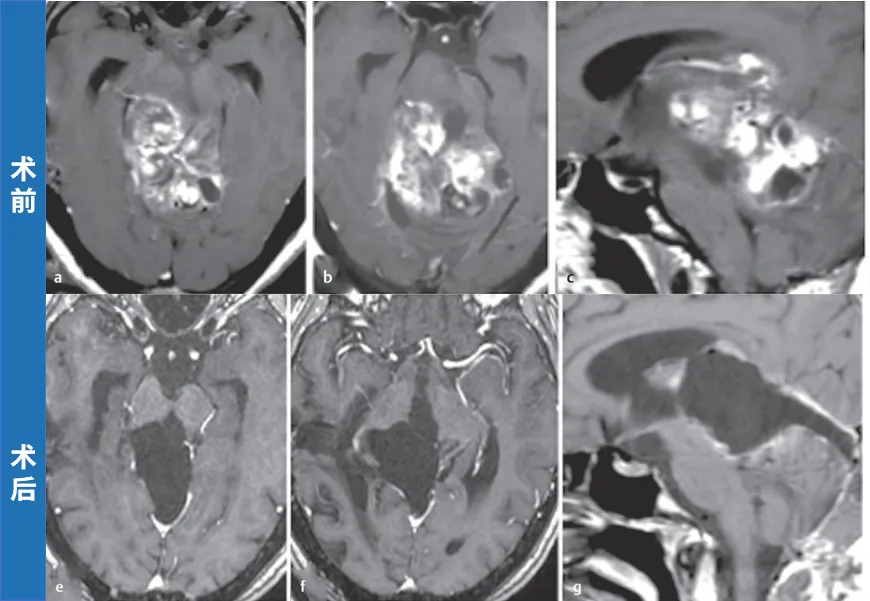

首次找到巴教授时,术前轴位(a、b)及矢状位(c)MRI显示肿瘤已极度增大,自中脑向双侧丘脑、脑桥及小脑广泛浸润。鉴于既往治疗未能有效控制肿瘤,实施手术。巴教授术中完整切除外生型毛细胞型星形细胞瘤,术后轴位(e、f)及矢状位(g)T1加权增强MRI证实肿瘤全切。

术后患者未出现新的神经功能障碍,恢复顺利。术后10年随访(h),患者状况良好,未见肿瘤复发。